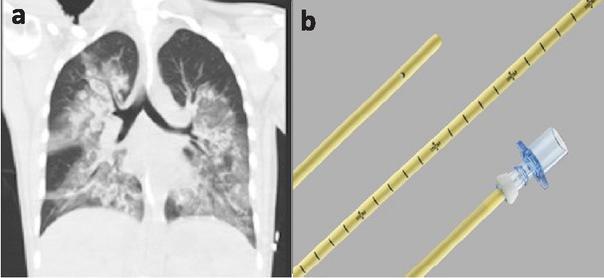

Fig.1